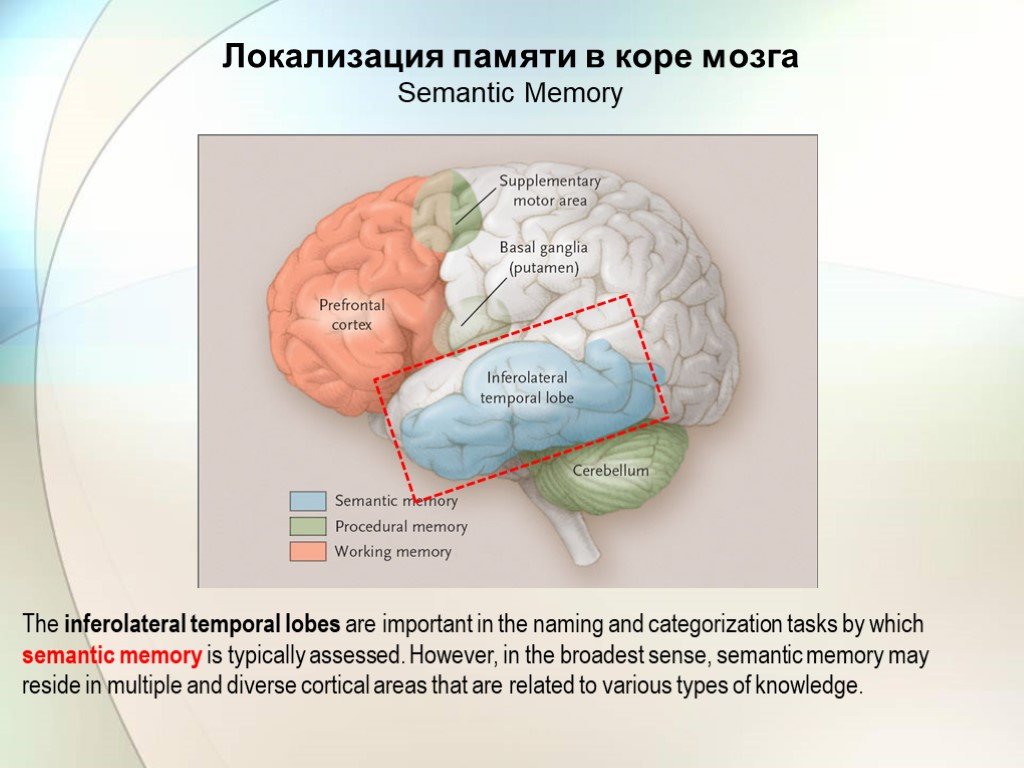

Физиология памяти: Механизмы и исследования